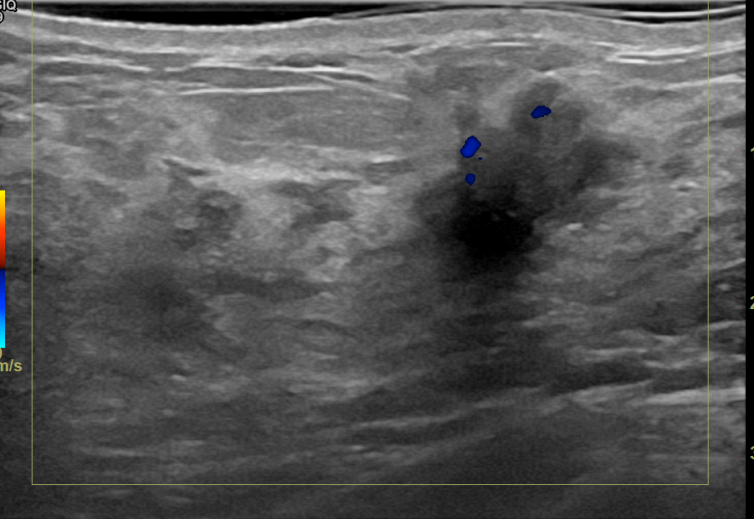

상기환자는 검진이상으로 조직검사위해 내원하신 50대중반

여성분으로 의심스러운 우측혹 조직검사 시행해 침윤성암으로 진단되었습니다